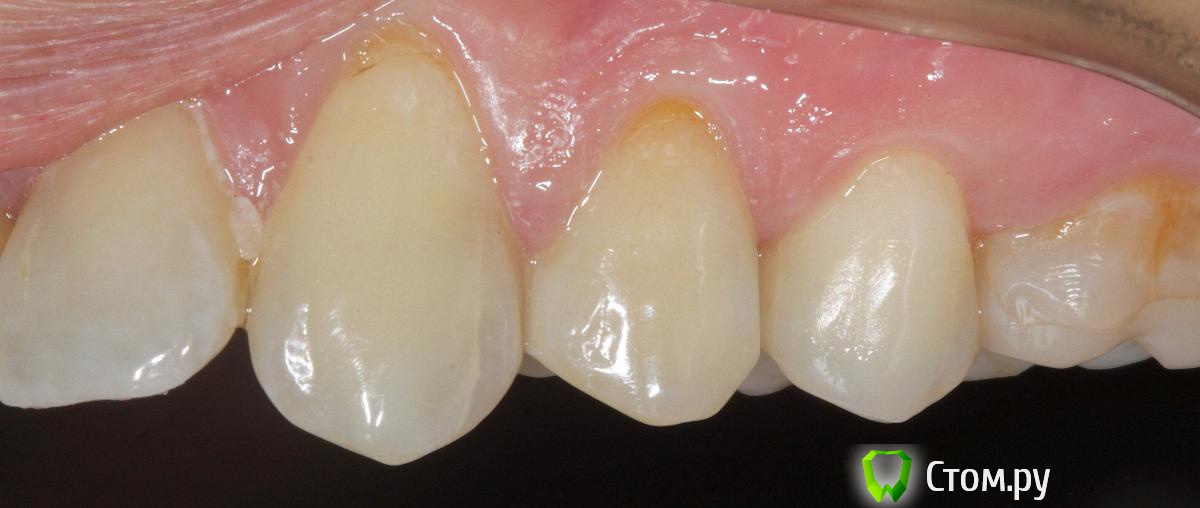

SDC Опубликовано 19 ноября, 2014 Поделиться Опубликовано 19 ноября, 2014 (изменено) Prettau, извините, не знаю, как редактировать название темы. Здравствуйте всем. В хирургическом много практиков, а по протетике - много теории)). Итак, разбавляю вино. (теория вечна)Протезирование премоляров коронками Преттау с нанесением керамики вестибулярно.Много фото, прошу прощения, поэтому без радикала, превью. Наверное даже так лучше, потому, что по клику откроются не сжатые фото, а радикал жмет.Протезирование в течение 2 недель. Фиксация на фуджи, без коффердама, но в сухих условиях (коффер не поставить по причине глубокий дистальной границы препарирования на обоих премолярах - глубокий кариес проксимальных поверхностей в анамнезе)Рг-контроль на предмет остатков цемента и на последнем фото удаленные излишки цемента на перчатке. Изменено 19 ноября, 2014 пользователем SDC 7 Ссылка на комментарий

SDC Опубликовано 20 ноября, 2014 Автор Поделиться Опубликовано 20 ноября, 2014 Отличный результат. Позвольте несколько вопросов.СВШ в боковых не ставите вообще,если да,то по какой причине?Как думаете антагонисты не будут истираться?Вы как-то меняете анатомию контакта при глубоких дефектах и недостатка сосочка?Спасибо.Спасибо Роман.По поводу штифтов. На самом деле, не имеет значения для меня.Важно, что не было титановых во фронтальном отделе (открываются при редукции тв.тк. небольшой объем композита вокруг штифта, что приводит к хрупкости билдапа и иногда металл.штифты светят через композит и керамику)Антагонисты истираться будут, а цирконий - нет. Что поделаешь.Сейчас мы с техником делаем нанесение вестибулярно и по скатам бугров, для уменьшения негативного эффекта повышенной прочности циркония и ускорения сдаваемости.контакт всегда площадочный, пятно контакта в корональной 1/4.Дефицит мягких тканей керамикой никогда не восполняем. Моделировка коронки максимально анатомична. Ссылка на комментарий